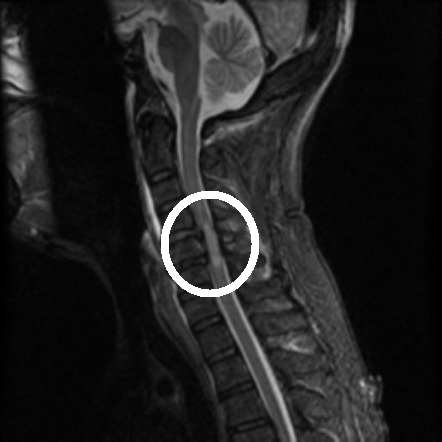

As you can see from the image above, central cord syndrome happens centrally in the spinal cord leaving the outer tissues/tracts intact. Now, if you didn’t know anything about the spinal cord you might think that this would be a rare type of injury, after all how do you injure the center of the cord without damaging the outer tissues? Unfortunately this is not the case. In fact, this is the most common type of incomplete spinal cord injury and accounts for almost 10% of traumatic spinal cord injury. Below is an MRI scan where I’ve highlighted (white circle) what a central cord injury looks like.

Sagittal view of acute traumatic non-hemorrhagic central cord syndrome. I’ve highlighted the damage with the white circle to make it easier to see